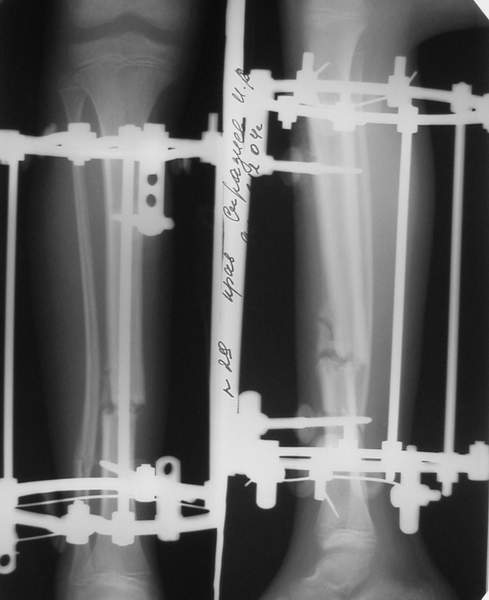

В аттачтах №№ 1 и 2 - примеры, когда 2 кольца не позволили послеоперационно

исправить смещение фрагментов большеберцовой (по ширине и вальгусное).

А казалось бы (#2) - поиграй на штангах и все влетит.

1

1a

2